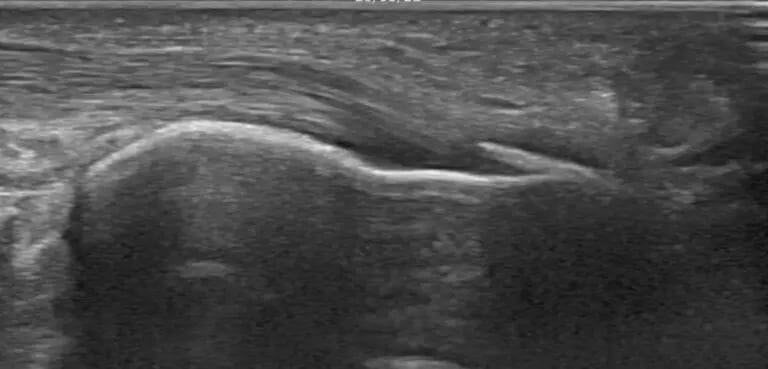

Además de la exploración física y los test diagnósticos, la ecografía nos ayuda a: localizar el depósito, valorar el estado del tendón y de los tejidos alrededor, elegir el tratamiento más adecuado y controlar la evolución.

La EPI se realiza con guía ecográfica para aplicar un estímulo local muy preciso en el tendón.